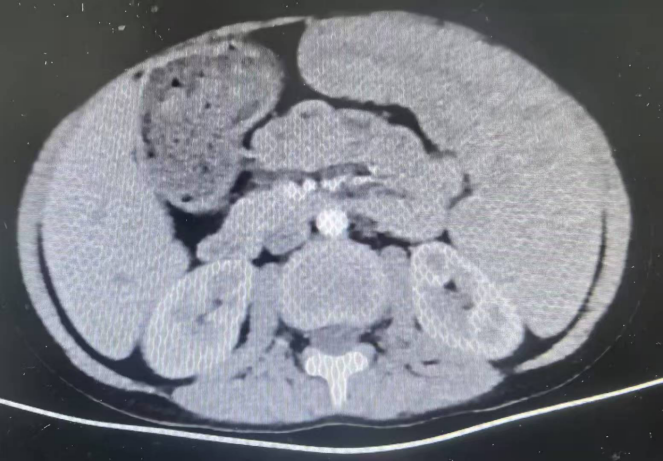

此次接受手术的患儿均为地中海贫血伴脾肿大,经小儿外科团队详细评估,患儿均符合脾切除手术指征,但考虑到儿童腹腔空间狭小、组织娇嫩,且家长对术后美观及康复速度有较高期待,团队决定采用“单孔腹腔镜技术”——仅在患儿脐部切开一个约2cm的小切口,通过专用器械完成脾脏游离、血管结扎及完整切除,最后将脾脏组织经脐部切口取出。

“单孔腹腔镜手术的关键在于‘精准’与‘协调’。”我院小儿外科主任窦俊锋介绍,脾脏血供丰富,周围毗邻胃、胰腺、结肠等重要器官,儿童腹腔操作空间仅为成人的1/3左右,术中需通过单一通道完成分离、止血、结扎等多步骤操作,对团队的解剖熟悉度、器械配合能力及应急处理水平要求极高。